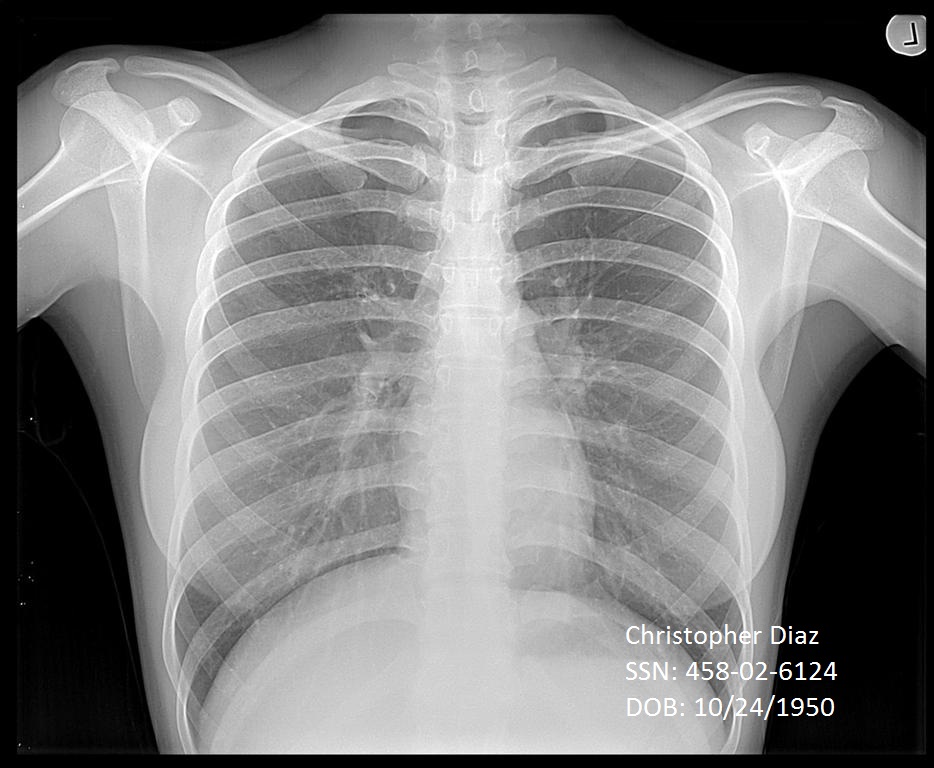

xray image